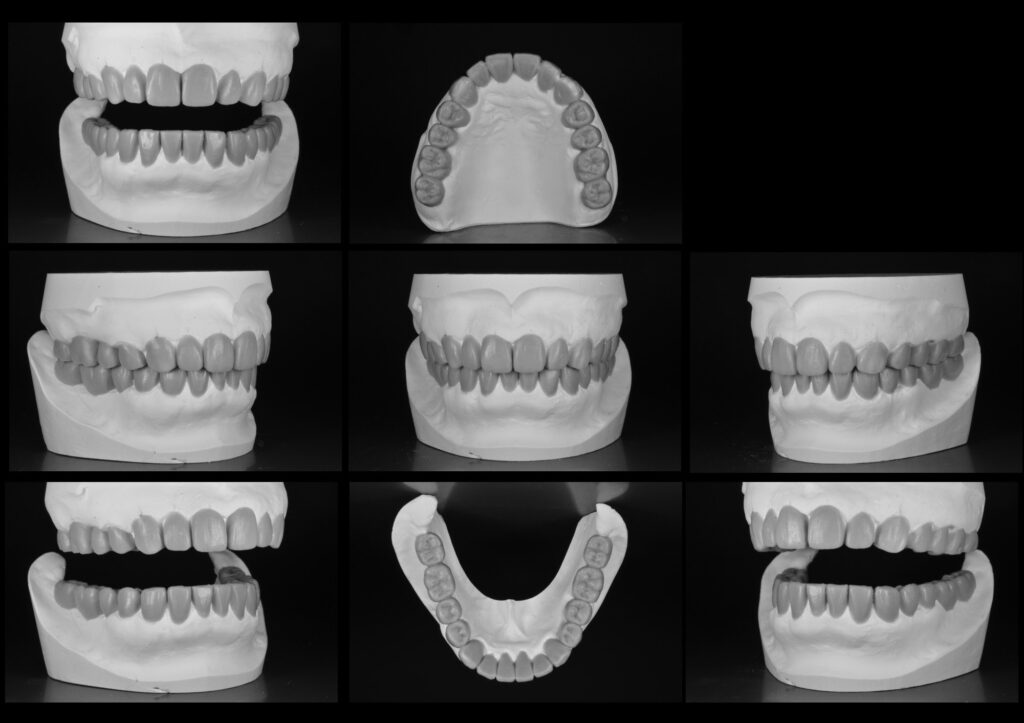

治療計画を練る上で、歯型を模型にして噛み合わせの器械(咬合器)上に患者様の状態を再現します。レントゲンやCT、写真を参考にし歯科用ワックスで治療のゴールをシミュレーションします。

問題となってる下の前歯の歯列から飛び出しを改善します。写真左上の顎を開けている模型を見ていただくと術前と比べ凹凸がなく、顎の動きの阻害しません。